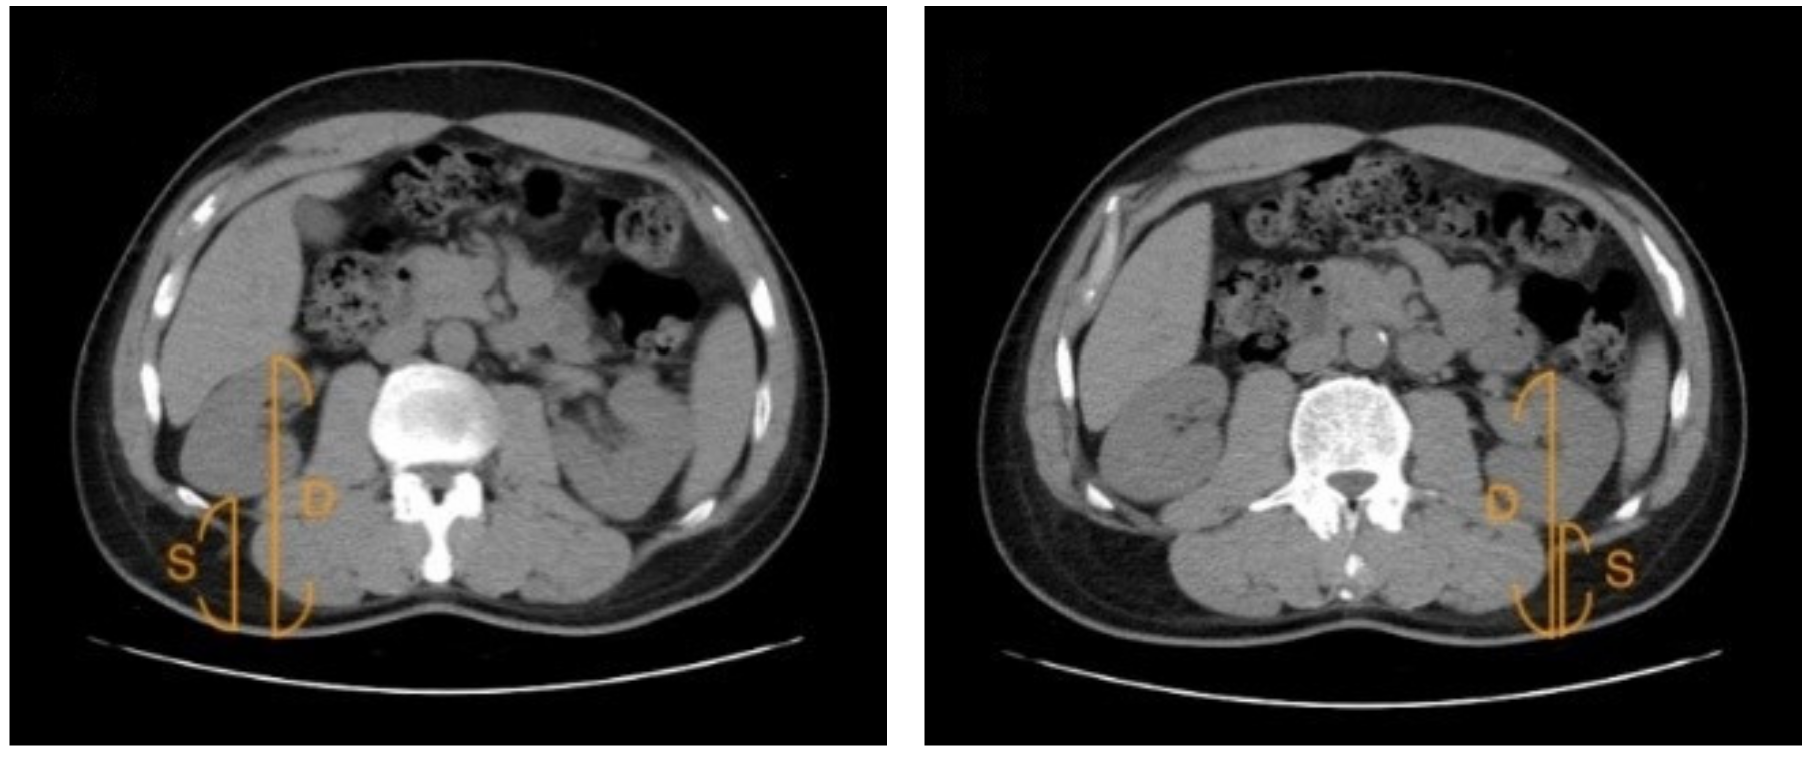

2.6. Assessment of Renal Depth by CT